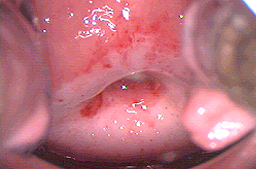

Se destruye la zona de riesgo a una profundidad que varía de 4 a 10 mm, dependiendo de cada paciente. Las lesiones que se localizan dentro de la zona de transformación requieren hasta 8 mm de profundidad, si se encuentran fuera de la zona de transformación (epitelio con células escamosas maduras de bajo riesgo para el cáncer) se da una profundidad de 4 mm. Lo anterior nos permite destruir la zona de riesgo y las lesiones displásicas periféricas con gran precisión, con la menor reducción de volumen del cérvix y por tanto con mínimo riesgo de secuelas. Se recomienda para lesiones de bajo grado de cualquier extensión o localización y para lesiones de alto grado periféricas (fuera del canal) en mujeres jóvenes. En las lesiones de alto grado que se extienden al canal endocervical se recomienda enviar cono para estudiar la posibilidad de lesiones más graves ocultas (cáncer) y por lo tanto no se deberá fotovaporizar dicha zona del canal. Cuando tenemos una colposcopía insatisfactoria ya que no es visible totalmente la lesión displásica por extenderse al canal endocervical, también se recomienda hacer un cono central para mandar hacer el estudio histopatológico.